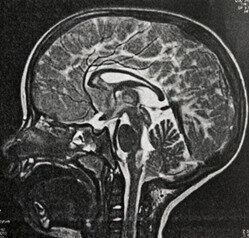

4. 生後9カ月のとき、突然激しいけいれん発作を起こした息子。遺伝子検査の結果、聞いたこともない病名に目の前が真っ暗に【アレキサンダー病・体験談】